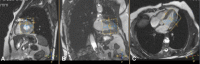

Cardiac energy status, measured as phosphocreatine (PCr)/adenosine triphosphate (ATP) ratio with 31P-Magnetic Resonance Spectroscopy (31P-MRS) in vivo, is a prognostic factor in heart failure and is lowered in cardiometabolic disease. It has been suggested that, as oxidative phosphorylation is the major contributor to ATP synthesis, PCr/ATP ratio might be a reflection of cardiac mitochondrial function. The objective of the study was to investigate whether PCr/ATP ratios can be used as in vivo marker for cardiac mitochondrial function. We enrolled thirty-eight patients scheduled for open-heart surgery in this study. Cardiac 31P-MRS was performed before surgery. Tissue from the right atrial appendage was obtained during surgery for high-resolution respirometry for the assessment of mitochondrial function. There was no correlation between the PCr/ATP ratio and ADP-stimulated respiration rates (octanoylcarnitine R2 < 0.005, p = 0.74; pyruvate R2 < 0.025, p = 0.41) nor with maximally uncoupled respiration (octanoylcarnitine R2 = 0.005, p = 0.71; pyruvate R2 = 0.040, p = 0.26). PCr/ATP ratio did correlate with indexed LV end systolic mass. As no direct correlation between cardiac energy status (PCr/ATP) and mitochondrial function in the heart was found, the study suggests that mitochondrial function might not the only determinant of cardiac energy status. Interpretation should be done in the right context in cardiac metabolic studies.